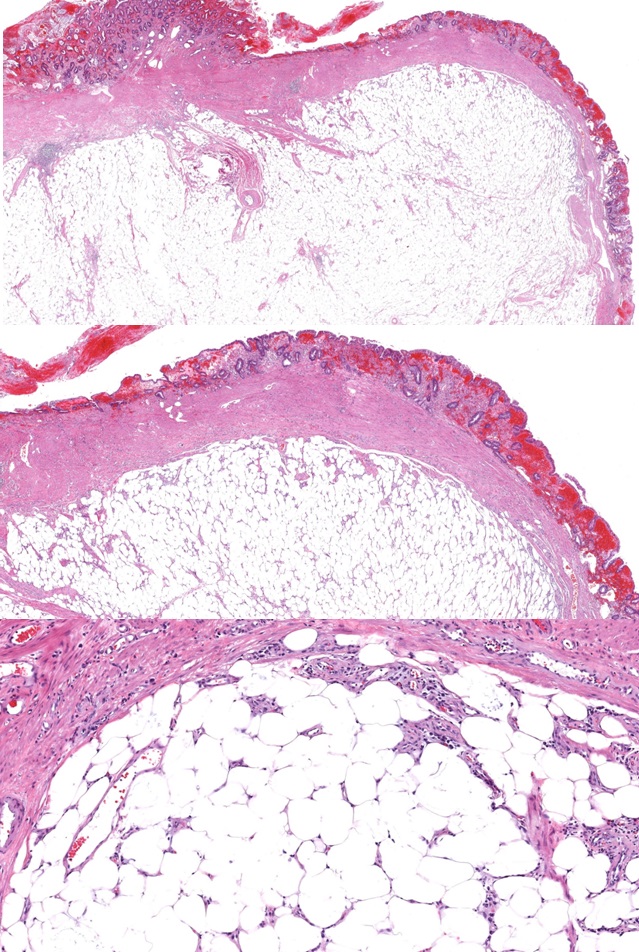

Se presenta el caso de un paciente de 68 años con invaginación intestinal secundaria a un lipoma submucoso de íleon. Se trata de una entidad rara en adultos y que suele ser debida a una lesión orgánica. La manifestación clínica se caracteriza por vómitos, dolor abdominal y melenas.

Se presenta el caso de un paciente al que tras la realización de una colonoscopia y un TAC abdominal, se realizó una resección ampliada de ciego e íleon terminal.